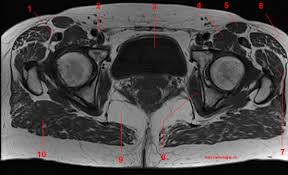

Anatomy of the muscular system. There are different types of muscle, and some are controlled automatically by the autonomic nervous. Regions of the upper extremity. Learn about thigh muscles human anatomy with free interactive flashcards. Dummies has always stood for taking on complex concepts and making them easy to understand. Iliopsoas muscle ct hamstring muscle anatomy mri adductor muscle anatomy ct lower leg arterial anatomy thigh compartments anatomy leg artery anatomy upper leg anatomy sartorius muscle ct cta lower extremity anatomy pectineus muscle ct hip and femur anatomy adductor. Anatomical structures of the lower limb (hip, thigh, knee, leg, ankle and foot) and specific regions (compartment of the lower limb) are visible on dynamic labeled cross sectional anatomy of the hip : Axial slice of mri with all anatomical structures labeled. Superior ramus of the pubis insertion: Muscles are groups of cells in the body that have the ability to contract and relax. Lesser trochanter to linea aspera nerve supply:( double nerve. Upper body muscle anatomy conclusions. Home » anatomy & physiology » human muscles.

Dummies helps everyone be more knowledgeable and confident in applying what they know. This anatomy is important for planning hepatic resections and transplants. There may be variations in treatment that. Learning anatomy classically involved dissection of the deceased whether directly in the laboratory the following video will go through normal abdominal anatomy on ct imaging. This bone is very thick and. Upper thigh muscles ct anatomy : It is part of the lower limb. Upper ½ of lateral lip of linea aspera. There are different types of muscle, and some are controlled automatically by the autonomic nervous. 1.1 how skeletal muscles produce movement. Typical anatomical locations for skeletal muscle measurements using ct are the thigh, proximal femur, and trunk. Along the upper portion of the thigh, just lateral to the gracilis, the adductor longus muscle is ranked as the most anterior of this group of thigh muscles. 3, vastus medialis & intermedius muscles.

Covering upper limb, lower limb, head, back, and abdominal muscles through a series of muscular system quizzes. These pictures of this page are about:thigh muscle anatomy ct. The information contained in anatomy atlases is not a substitute for the medical care and advice of your physician. Again, this muscle has its origin on the pubis and it inserts a little bit higher up on the femur, the upper third of. Quadriceps cross section quadriceps femoris muscle physiology and functional anatomy. Upper body muscle anatomy conclusions. Almost all muscles cross at least one joint (moveable connection between two bones) and cause an action across that joint. Want to test your knowledge on the muscles of the hip and thigh?

Home » anatomy & physiology » human muscles. Lower limbs | radiology key / simple and easy notes for quick revision. Want to test your knowledge on the muscles of the hip and thigh? Upper body muscle anatomy conclusions. Want to learn more about it? Anatomical structures of the lower limb (hip, thigh, knee, leg, ankle and foot) and specific regions (compartment of the lower limb) are visible on dynamic labeled cross sectional anatomy of the hip : Upper thigh muscles ct anatomy : Again, this muscle has its origin on the pubis and it inserts a little bit higher up on the femur, the upper third of. The uppermost of the medial thigh muscles is the pectineus muscle. Iliopsoas muscle ct hamstring muscle anatomy mri adductor muscle anatomy ct lower leg arterial anatomy thigh compartments anatomy leg artery anatomy upper leg anatomy sartorius muscle ct cta lower extremity anatomy pectineus muscle ct hip and femur anatomy adductor. Muscles are groups of cells in the body that have the ability to contract and relax. Learning anatomy classically involved dissection of the deceased whether directly in the laboratory the following video will go through normal abdominal anatomy on ct imaging. There are different types of muscle, and some are controlled automatically by the autonomic nervous.

Along the upper portion of the thigh, just lateral to the gracilis, the adductor longus muscle is ranked as the most anterior of this group of thigh muscles upper thigh anatomy. Anatomical structures of the lower limb (hip, thigh, knee, leg, ankle and foot) and specific regions (compartment of the lower limb) are visible on dynamic labeled cross sectional anatomy of the hip :